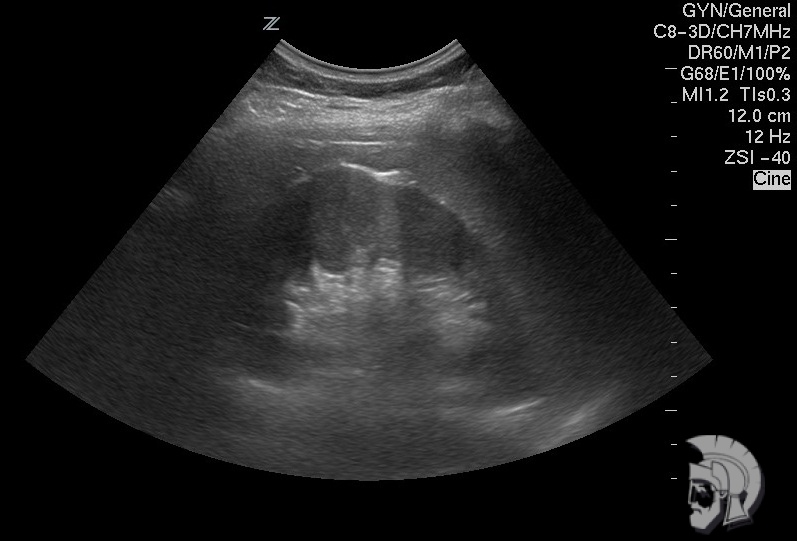

УЗИ почек показывает правильность расположения почек, движение почек согласно фазам дыхания, структуру почек и наличие гемангиомы, кисты, опухолевых образований, расширение чашечно-лоханочной системы, наличие «камней», особенности кровоснабжения и состояния сосудов почек.

Использование ультразвуковых аппаратов экспертного класса с режимами энергетического допплера и цветового ДОППЛЕРа позволяет врачам Курортной клиники мужского здоровья выявлять патологические изменения почек и мочевого пузыря на ранних этапах.